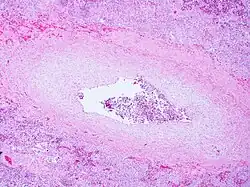

Pulmonary veno-occlusive disease-Intimal fibrosis with marked narrowing of lumen of a large pulmonary vein

Pulmonary veno-occlusive disease may have a genetic basis. Published reports have indicated fatal occurrences that appeared to possess a familial pattern, more to the point, a germline mutation.[7] The pathophysiology of veno-occlusive disease culminates in occlusion of the pulmonary blood vessels. This could be due to edematous tissue (sclerotic fibrous tissue). Thickening is identified in lobular septal veins, also dilatation of lymphatics happens. Furthermore, alveolar capillaries become dilated (due to back-pressure).[8]